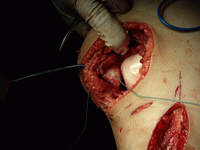

(1)局限性軟骨切除加鑽孔術:為目前仍較常採用的基本術式可採用關節鏡或髕前內側或前外側切口,顯露後以刨刀削除變性的軟骨暴露軟骨下骨板,用1~2mm鑽頭鑽孔數個本手術的目的是使來自骨內的纖維肉芽組織填補缺損軟骨最後化生成纖維軟骨。鑽孔也能釋放骨內壓使疼痛得到緩解。

(5)軟骨移植:包括自體軟骨細胞移植和自體骨軟骨塊蜂窩狀移植(又稱馬賽克軟骨移植術)。前者取患者自體軟骨進行體外軟骨細胞培養,用組織工程方法將培養增殖後的軟骨細胞植入病灶區,再用骨膜覆蓋目前全世界已有1000餘例的成功報導自體骨軟骨塊馬賽克移植術用特殊器械鑿取膝關節股骨髁非負重區骨軟骨組織是將這些柱狀的骨軟骨塊移植至負重區軟骨,呈馬賽克樣鑲嵌移植。據報導優良率可達80%。以上兩種方法均可在關節鏡下進行。